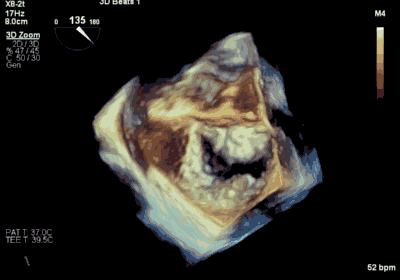

▲ 术后超声检查显示轻度二尖瓣反流

王焱、王斌教授团队通过术前和台北荣民总医院(Taipei Veterans General Hospital)宋思贤教授进行了详细的讨论并制定了最优的手术策略,同时术中视频连线获得宋思贤教授的技术支持,吃瓜网 超声内科苏茂龙教授负责术中超声心动图引导。患者全麻以后,在经食道超声心动图和X射线引导下,经股静脉入路,将MitraClip瓣膜夹顺利送至二尖瓣前后叶交界中心处,成功捕捉二尖瓣前叶A2和后叶P2,经超声心动图反复确认瓣叶夹持牢固后,测定有效夹持长度11mm,评估反流量降至微量,释放瓣膜夹,超声心动图评估瓣膜夹位置和功能良好,测定左房压降至11/6mmHg,再次评估反流量仍为微量,手术顺利完成。